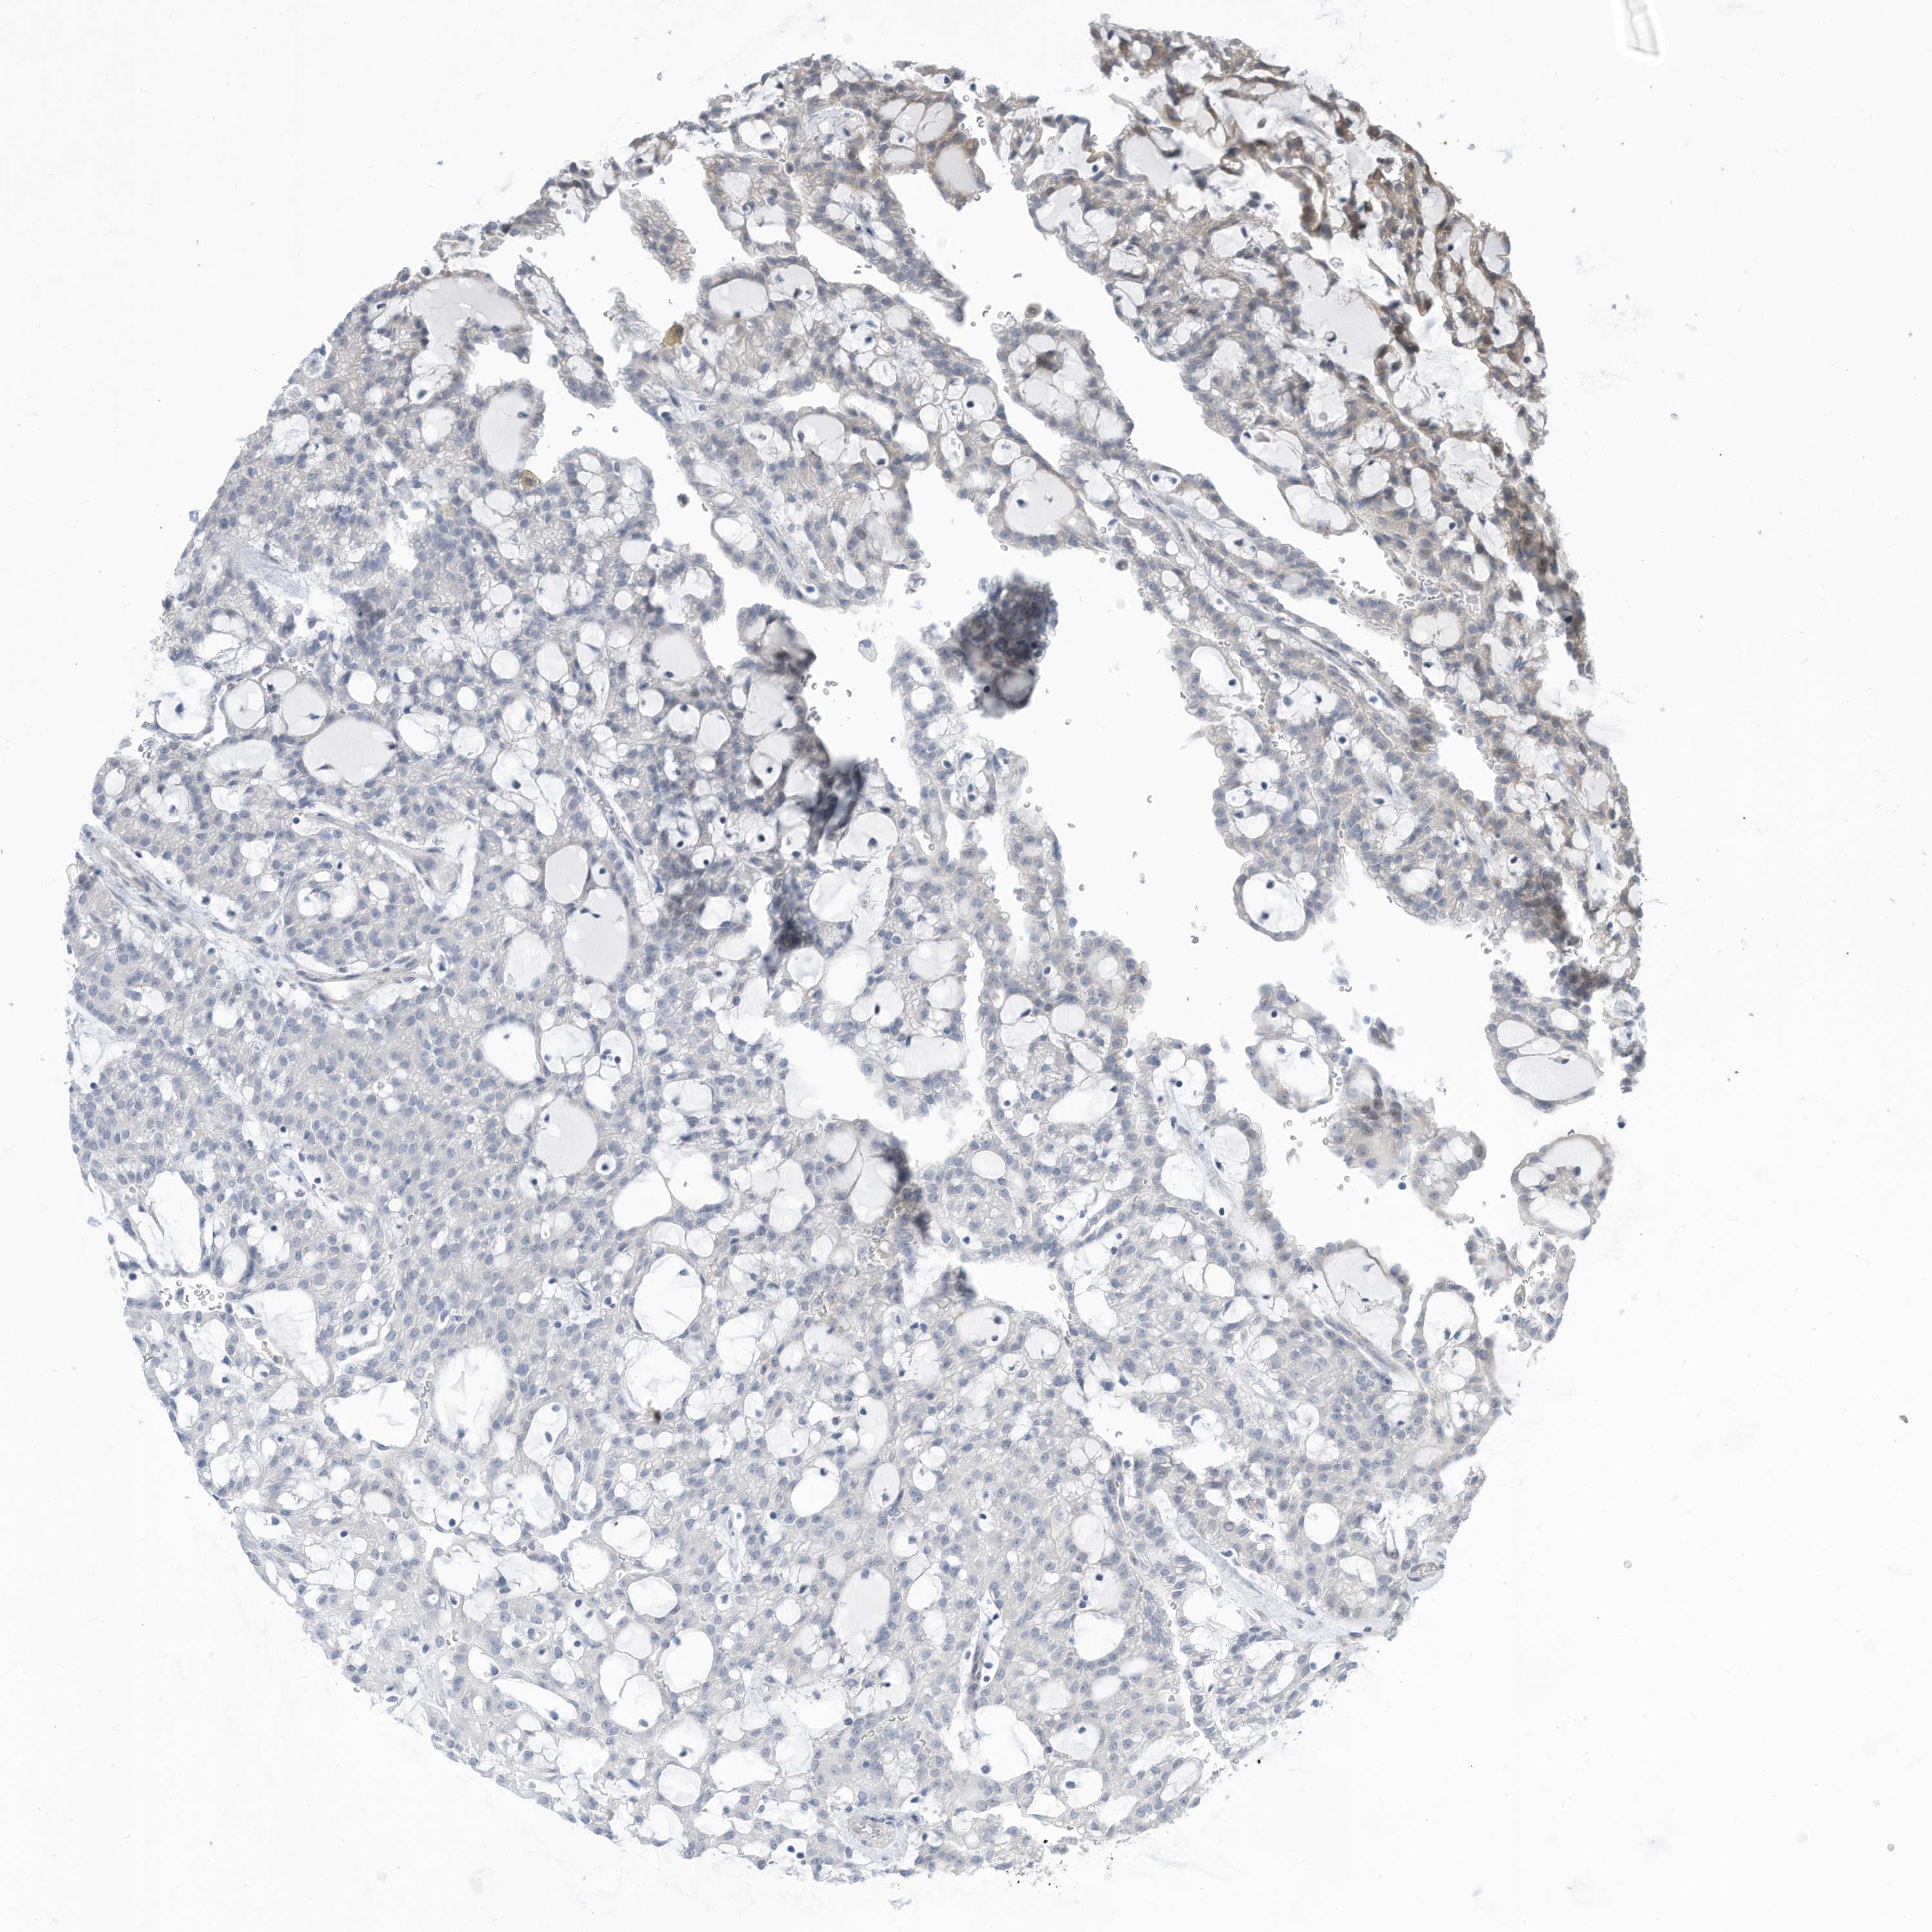

KIDNEY RENAL PAPILLARY CELL CARCINOMA (TCGA) - Interactive survival scatter ploti

The Survival Scatter plot shows the clinical status (i.e. dead or alive) for all individuals in the patient cohort, based on the same data that underlies the corresponding Kaplan-Meier plots. Patients that are alive at last time for follow-up are shown in blue and patients who have died during the study are shown in red.

The x-axis shows the expression levels (FPKM) of the investigated gene in the tumor tissue at the time of diagnosis. The y-axis shows the follow-up time after diagnosis (years). Both axes are complimented with kernel density curves demonstrating the data density over the axes. The top density plot shows the expression levels (FPKM) distribution among dead (red) and alive patients (blue). The right density plot shows the data density of the survived years of dead patients with high and low expression levels respectively, stratified using the cutoff indicated by the vertical dashed line through the Survival Scatter plot. This cutoff is automatically defined based on the FPKM cutoff that minimizes the p-score. The cutoff can be changed by dragging the vertical line or by entering a cutoff value in the square labeled "Current cut-off".

Under the Survival Scatter plot the p-score landscape (black curve; left axis) is shown together with dead median separation (red curve; right axis). Dead median separation is the difference in median mRNA expression between patients who have died with high and low expression, respectively. It is calculated as follows: median FPKM expression of dead patients with high expression - median FPKM expression of dead patients with low expression. This is intended to aid the user in visually exploring custom cutoffs and the associated p-scores and dead median separation.

Individual patient data is displayed and can be filtered by clicking on one or more of the category buttons on the top of the page. Categories describing expression level and patient information include: high, low, alive, dead, female, male and tumor stages. The scale of the x-axis can be toggled between linear and log-scale by clicking on the "x log" button. Mouse-over function shows TCGA ID, patient information and mRNA expression (FPKM) for each patient.

& Survival analysisi

Kaplan-Meier plots summarize results from analysis of correlation between mRNA expression level and patient survival. Patients were divided based on level of expression into one of the two groups "low" (under cut off) or "high" (over cut off). X-axis shows time for survival (years) and y-axis shows the probability of survival, where 1.0 corresponds to 100 percent.

ZNF292 is not prognostic in Kidney Renal Papillary Cell Carcinoma (TCGA)

Best expression cut offi

Based on the FPKM value of each gene, patients were classified into two groups and association between prognosis (survival) and gene expression (FPKM) was examined. The best expression cut-off refers the FPKM value that yields maximal difference with regard to survival between the two groups at the lowest log-rank P-value. Best expression cut-off was selected based on survival analysis .

When clicking on this number, the vertical dashed line indicating cut-off, the interactive survival plot, and the Kaplan-Meier curve will be adjusted to show results based on the best expression cut-off.

: 3